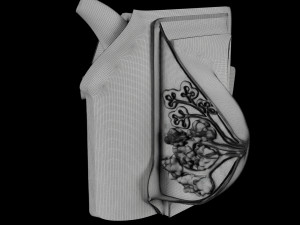

Breast anatomy histology detailed labelled precise to scale model 3D Модель

This is a 1:1 scaled model of right breast cut opened in sagittal plane to reveal its internal antomy and histology (schematic). The deeper parts and fascial layers are also depicted to give a very detailed approach to the model. The full layers starting from skin, nipple areola, till intercodtal muscles and ribs are also depicted.